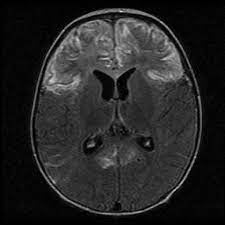

Brain mri—increased t2 signal intensity in frontotemporal region → viral (hsv) encephalitis.

In children older than 3 months and in adults brain biopsy: Herpesviral encephalitis, or herpes simplex encephalitis (hse), is encephalitis due to herpes simplex virus. • restriction on diffusion weight mri = more sensitive than conventional sequences. Misra uk, hashmi aa, kalita j. Diagnostic uncertainty and empirical management in pcr negative encephalitis. It is a severe condition brain mri may show limbic encephalitis (55) or diffuse t2 and dwi hyperintensities in the white matter, associated with restricted diffusion (54). Herpes simplex encephalitis occurs as 2 distinct entities: Mri is the imaging of choice in suspected cases of viral encephalitis, although ct scanning may be used where mri facilities are not available. The patient had initially improved after medical treatment. Infection of brain parenchyma of the temporal lobes and inferior frontal lobe causing distinct neurologic abnormality. Dhawan a, kecskes z, jyoti r, kent al. Associated with hsv encephalitis (strong evidence). In addition, because of the involvement of the.

It is a severe condition brain mri may show limbic encephalitis (55) or diffuse t2 and dwi hyperintensities in the white matter, associated with restricted diffusion (54). Brain mri—increased t2 signal intensity in frontotemporal region → viral (hsv) encephalitis. Associated with hsv encephalitis (strong evidence). Provided cranial imaging has excluded any contraindications such as a space occupying lesion or severe cerebral oedema and brain shift, a csf. Having said that, mri with contrast is considered the most sensitive imaging modality, and findings are present in over half of individuals 8. In addition, because of the involvement of the. We performed volumetric measurements of the left and right temporal lobes and of cerebral oedema. Herpes simplex encephalitis occurs as 2 distinct entities: The study analysed serially acquired magnetic resonance images (mri), of patients with acute hsv encephalitis who had neuroimaging repeated within four weeks of the first scan. Pregnancy the most common cause of encephalitis in newborns is vaginal delivery from a mother who is infected with herpes simplex virus 2 (hsv 2). There is no particular age, sex, or seasonal predilection. Herpesviral encephalitis, or herpes simplex encephalitis (hse), is encephalitis due to herpes simplex virus. Severe infection, particularly untreated herpes simplex virus (hsv) encephalitis, can cause brain hemorrhagic necrosis.